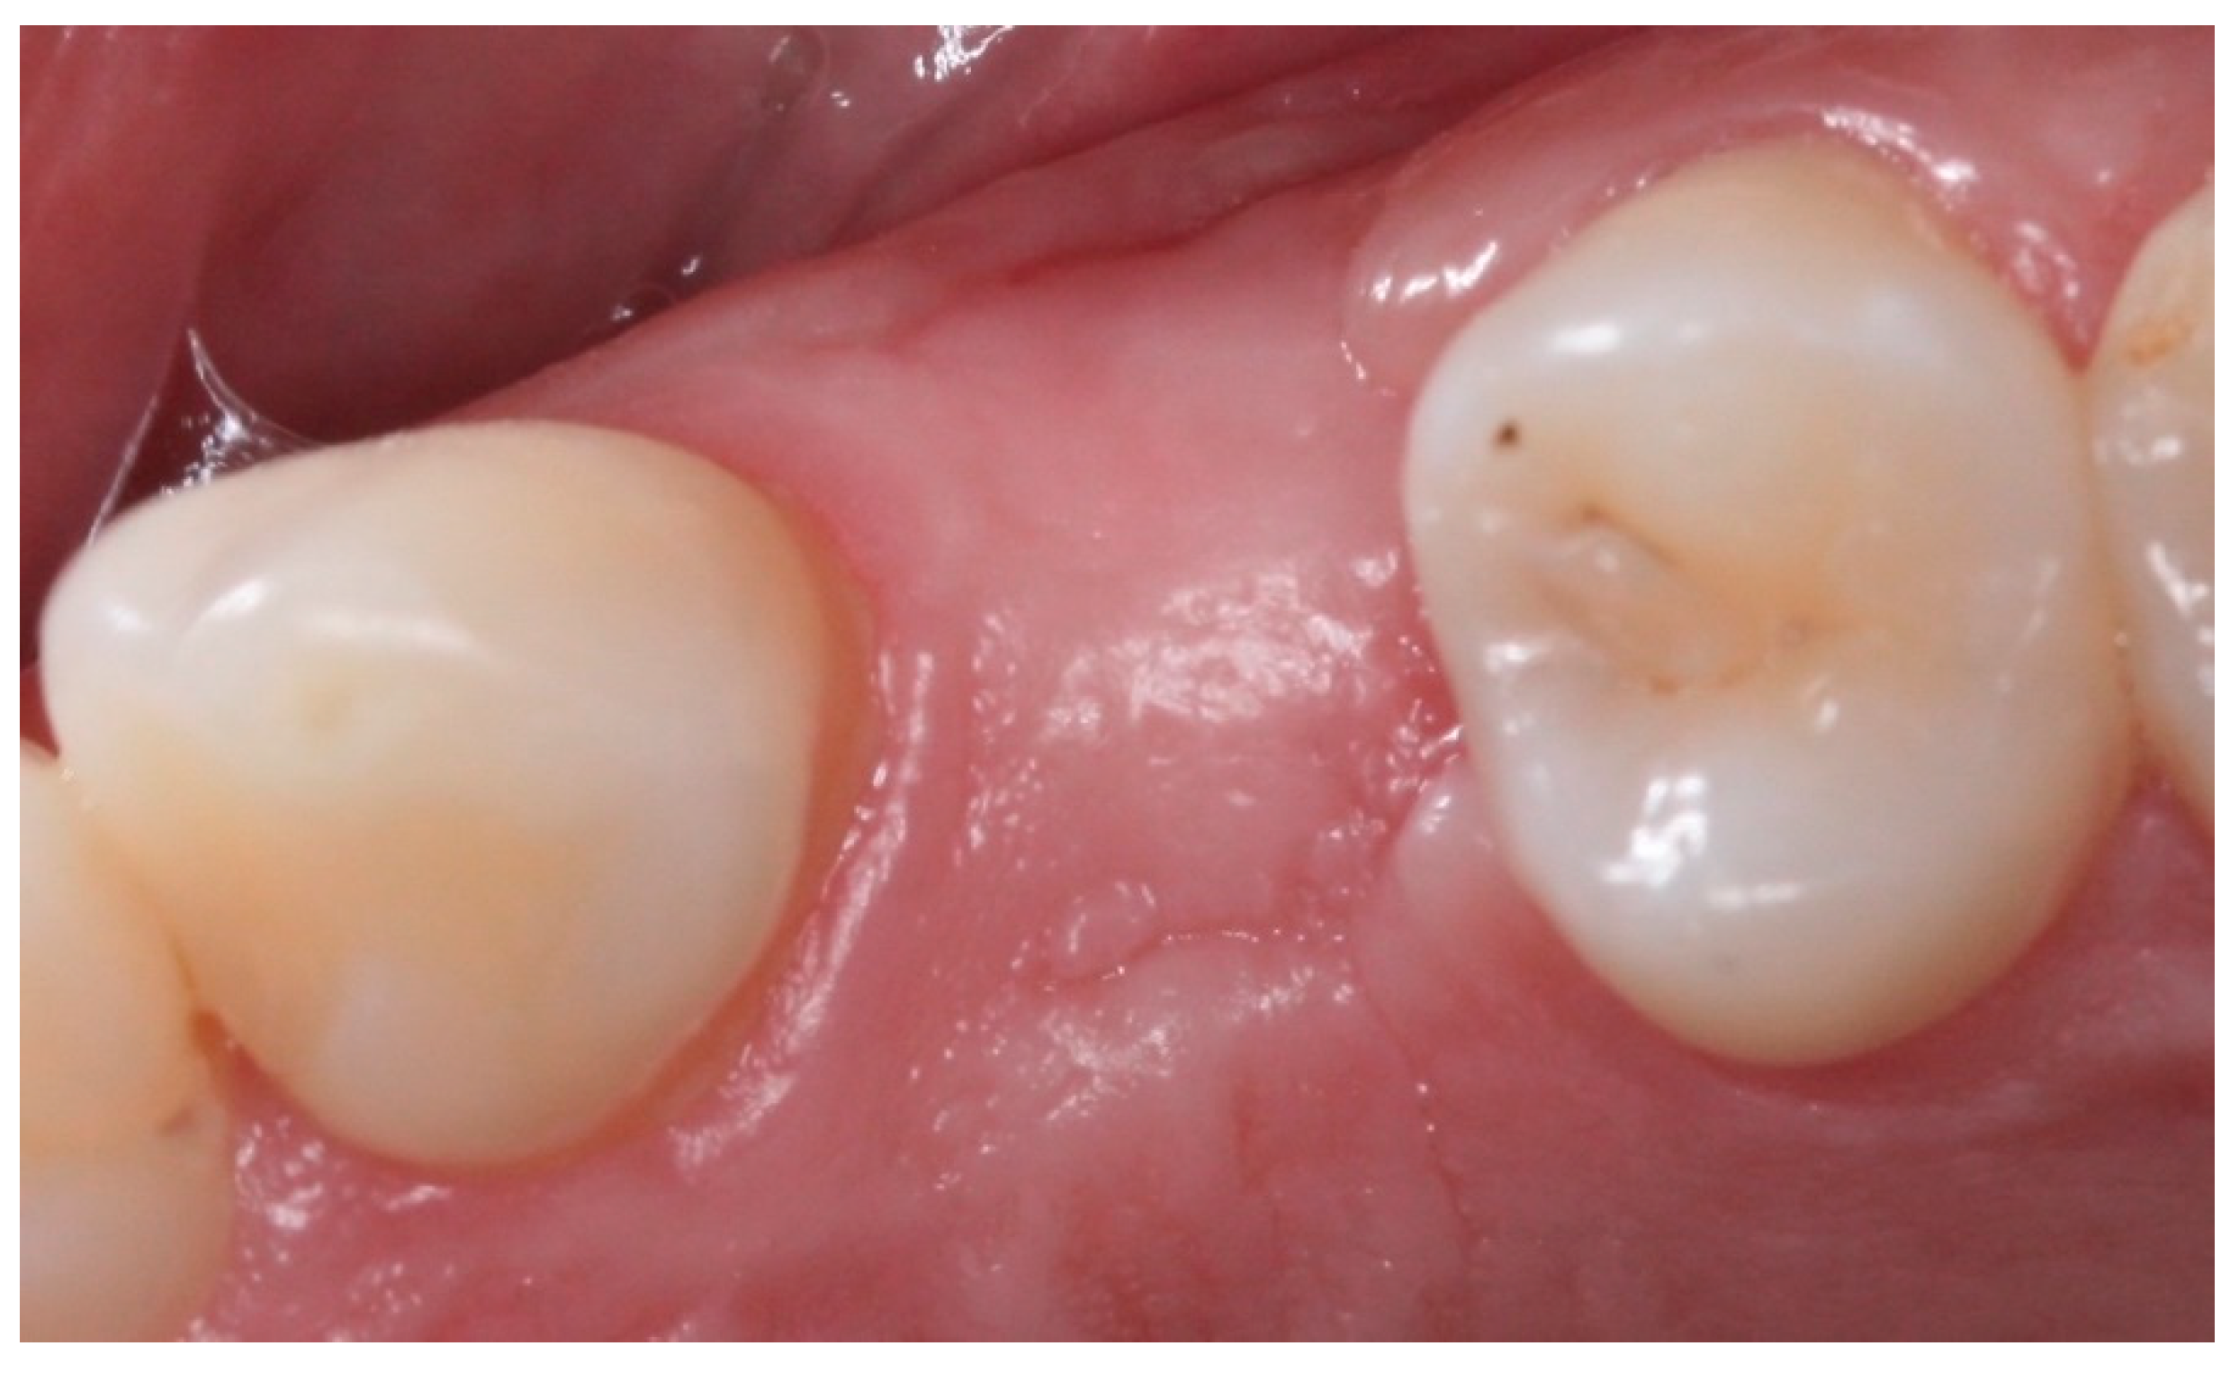

2. Materials and Methods

2.4. Groups